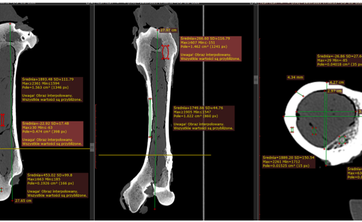

Dr Leszek Pyziak wygłosił referat nt. Korelacja wyników Ilościowej tomografii komputerowej (QCT) gęstości mineralnej kości zapisanych w skali Haunsfield